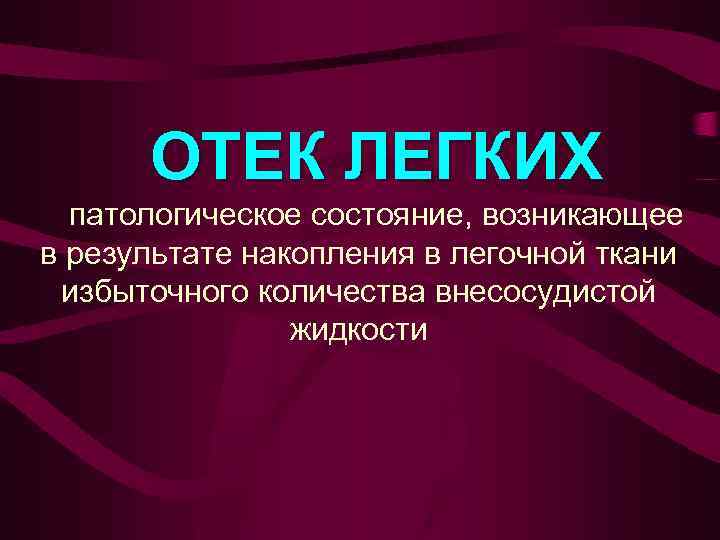

ОТЕК ЛЕГКИХ патологическое состояние, возникающее в результате накопления в легочной ткани избыточного количества внесосудистой жидкости

ОТЕК ЛЕГКИХ патологическое состояние, возникающее в результате накопления в легочной ткани избыточного количества внесосудистой жидкости